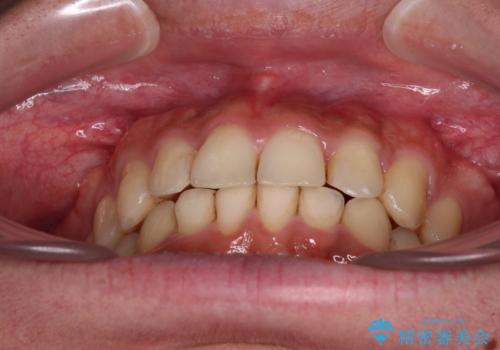

前歯のデコボコをスッキリ改善 インビザライン矯正

- 上下前歯のデコボコを気にして来院された患者様です。

全体的に叢生は軽度であったため、インビザラインにて矯正治療を行うこととしました。

デコボコの改善はもちろん、下顎前歯が隠れてしまうディープバイトも一緒に改善することができ、奥歯への負担を軽減することができました。